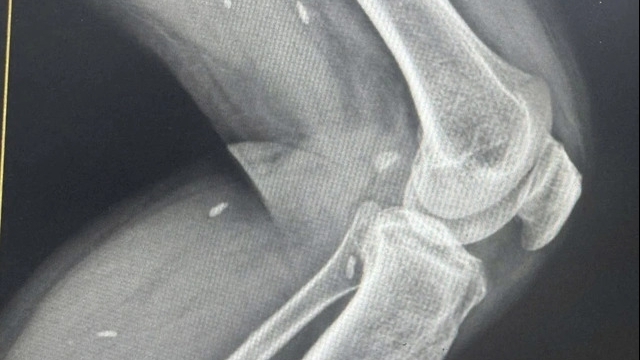

Bệnh nhân 91 (nam phi công người Anh) là ca nhiễm Covid-19 nặng nhất tại Việt Nam. Bệnh nhân này đã có nhiều giai đoạn nguy kịch với tiên lượng rất xấu. Tuy nhiên trong 10 ngày qua, sức khỏe của bệnh nhân đã có những chuyển biến rất tốt và đang hồi phục. Cho đến sáng 4/7/2020, Việt Nam chưa có ca tử vong do dịch Covid-19 và là quốc gia hiếm hoi có hơn 300 ca mắc nhưng không có ca nào tử vong.